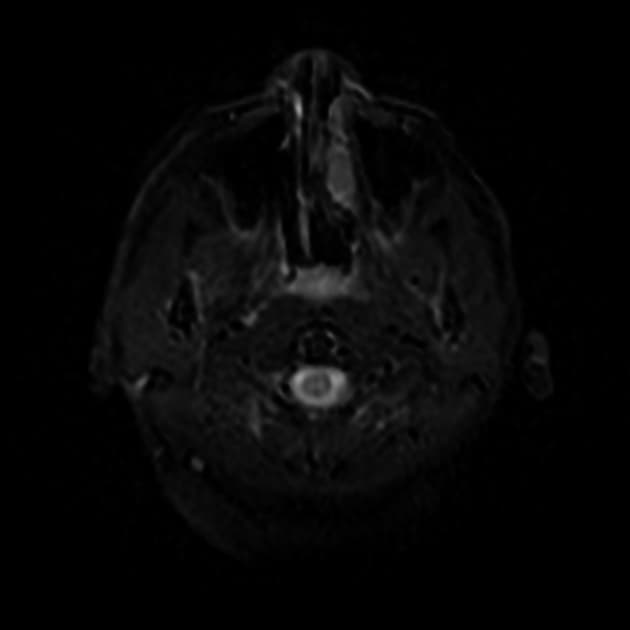

Trên cộng hưởng từ: có phù lan tỏa (oedema) ở bán cầu tiểu não phải. Tổn thương giảm tín hiệu trên T1, tăng tín hiệu trên T2 và FLAIR.

-

Hình ảnh khuếch tán (DWI) cho thấy tín hiệu tăng nhẹ, với khuếch tán thuận lợi trên bản đồ ADC (hiệu ứng T2 shine-through).

Có biến dạng cấu trúc nhẹ (mild distortion) ở phía bên phải thân não, nhưng không có xóa não thất (effacement) hay giãn não thất (hydrocephalus).

Không thấy tăng quang (enhancement) bất thường.

Không thành phần dạng nốt (nodular components).

Không thành phần xuất huyết (haemorrhagic components).

Đặc điểm hình ảnh phù hợp với viêm tiểu não cấp tính (acute cerebellitis), đặc biệt trong bối cảnh lâm sàng này.